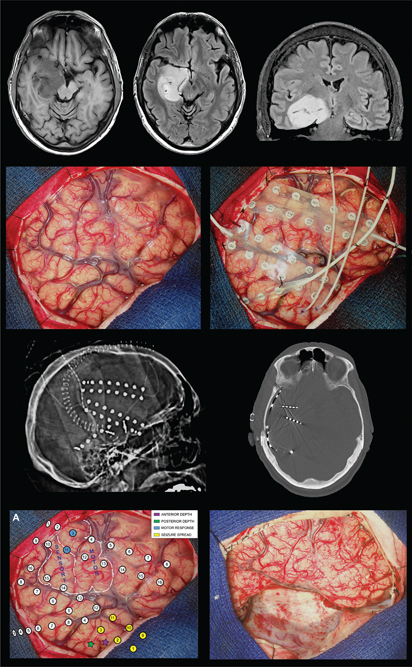

Different surgical treatment options as well as advanced imaging modalities are available for patients with BTRE. Intraoperative cortical brain mapping with electrocorticography, radiosurgery, and laser interstitial thermal therapy are additional surgical techniques that can be effectively utilized in BTRE. EEG mapping is also another modality that can be beneficial for identifying the epileptogenic focus. Epileptogenic foci can be identified within or overlying the tumor, the peritumoral tissue, and even distant areas away from the tumor (Figure 2) (61, 62). The extent of tumor resected directly correlates with seizure freedom; however, patients may benefit from subtotal resection if the epileptic focus was identified before the resection, especially if the tumor is in eloquent areas of the brain (62). It is essential to identify patients where the tumor is not the primary epileptogenic focus, as they may benefit from a combined approach encompassing both tumor resection and epilepsy surgery (61).

Fig 2

Figure 2. Surgical management of brain tumor-related epilepsy. This patient presented with recurrent seizures and a non-enhancing mass in the right medial temporal region (top row). Intraoperative photographs during intracranial electrode implantation (second row). Postsurgical CT scan showing placement of subdural grid electrodes and depth electrodes (third row). Intraoperative photographs showing intracranial electrode arrays with cortical mapping results and following resection of the tumor and epileptogenic tissue (bottom row).